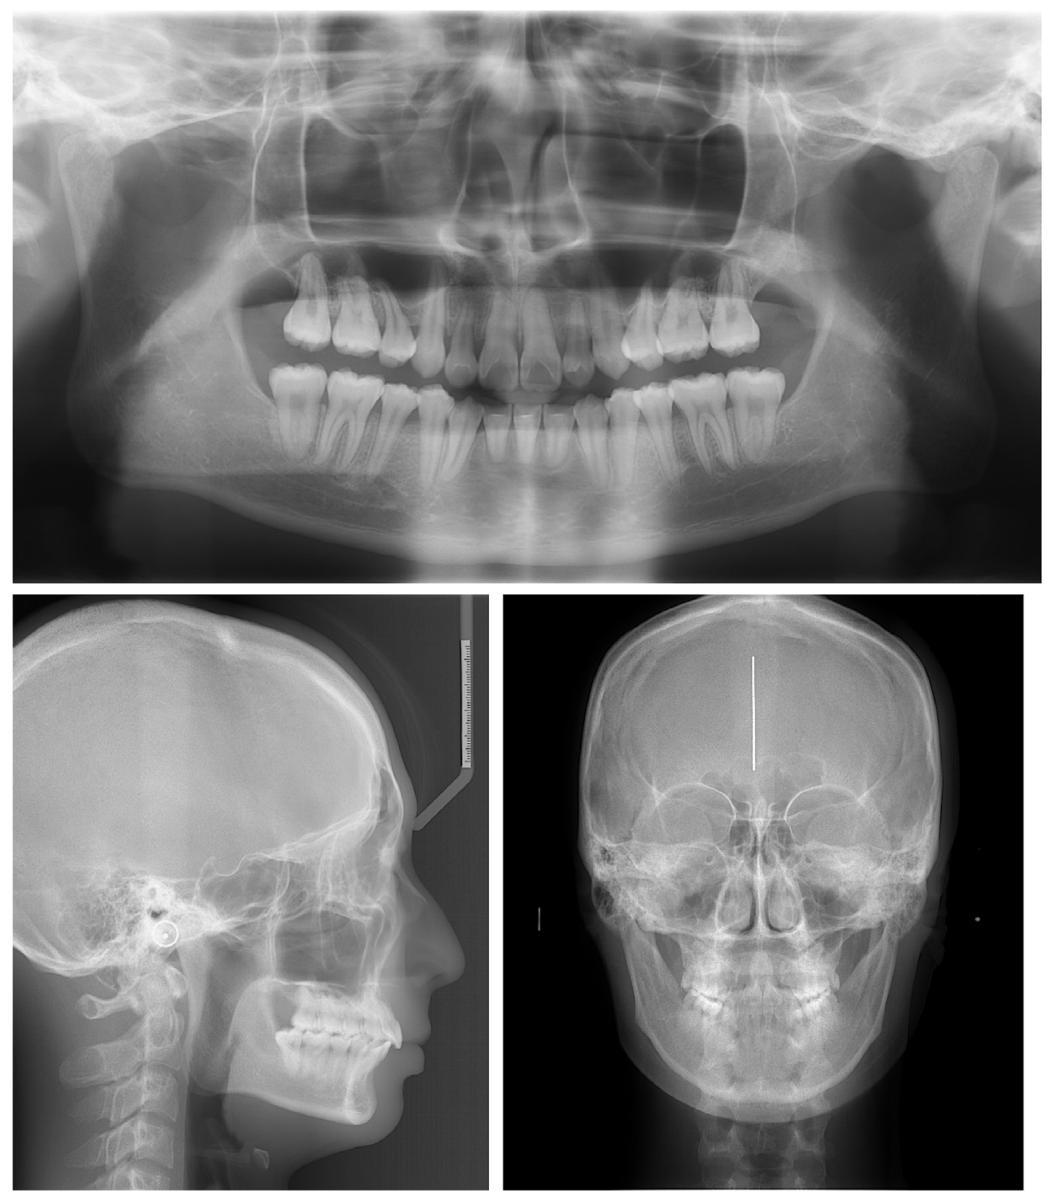

❸ 影像学验证

✅ 头影测量:上切牙唇倾度显著改善(U1-FH角从142.5°→114.9°),下颌逆时针旋转,骨性关系更协调

✅ 全景片:牙根平行度良好,牙周组织健康

治疗后X线片显示牙列与骨骼关系优化